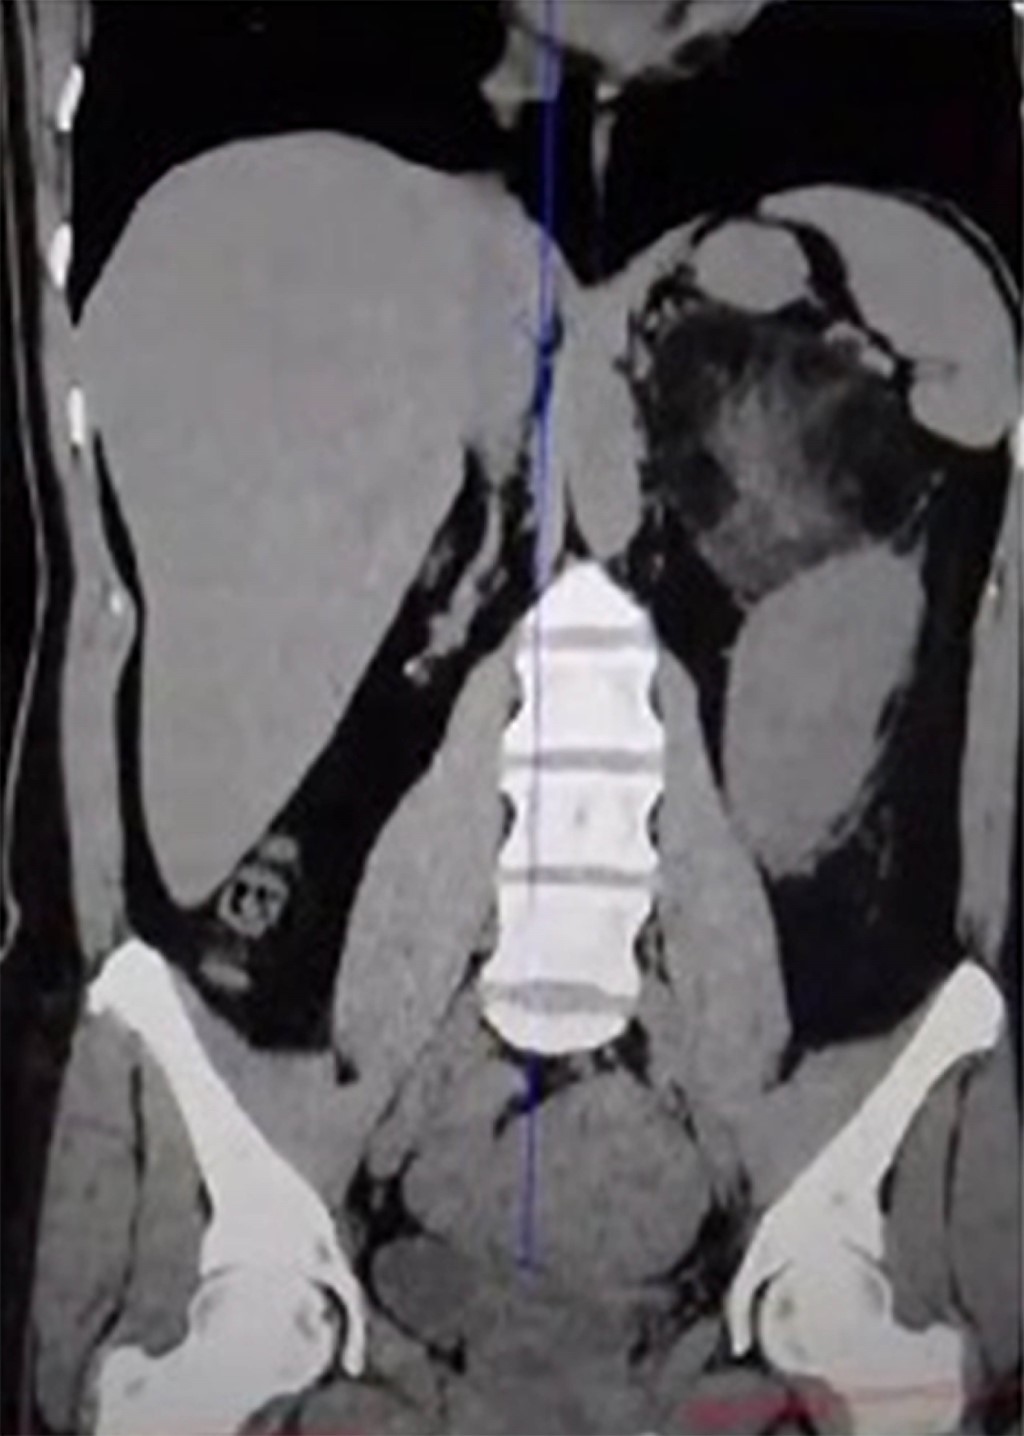

Se realizó tomografía abdominal que reveló neoformación en glándula suprarrenal izquierda de 9.1 × 7.9 × 8.1 centímetros (Figuras 1 y 2). Por lo que se decidió resección quirúrgica por vía laparoscópica.3

La tomografía es la modalidad más eficaz para su detección, en la cual se pueden observar masas suprarrenales heterogéneas bien circunscritas, con alta cantidad de grasa. Los valores de atenuación oscilan entre –20 y –30 HU, sugiriendo una mezcla de componentes adiposos y mieloides. Además, presenta calcificaciones en el 20% de los pacientes.5

Figura 1

Figura 2